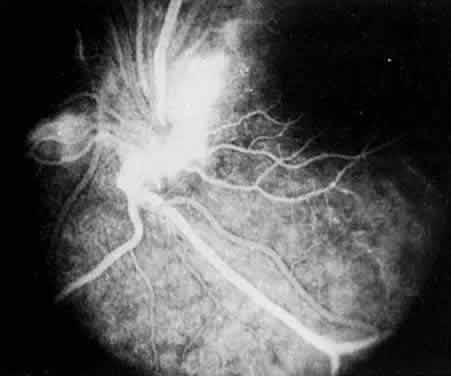

Retinal detachment, vitreous hemorrhage, optic disc swelling, and dragging of the optic disc vessels caused by contraction and neovascularization of cyclitic membranes occur in less than 10% of cases.13,52,53 Periphlebitis has been reported in about 21% of cases.52 Neovascularization of the optic disc53–55 and peripheral retina56 can also occur (Fig. 7). Coat's-like response has been reported in pars plantitis.57 Band keratopathy, glaucoma, and retinoschisis may develop as late sequelae in pars planitis.13

Fig. 7. Pars planitis. Fluorescein angiogram of neovascularization of the optic disc.

Fig. 6. Pars planitis. Fluorescein angiogram of pars plana membrane showing diffuse leakage indicating neovascularization.